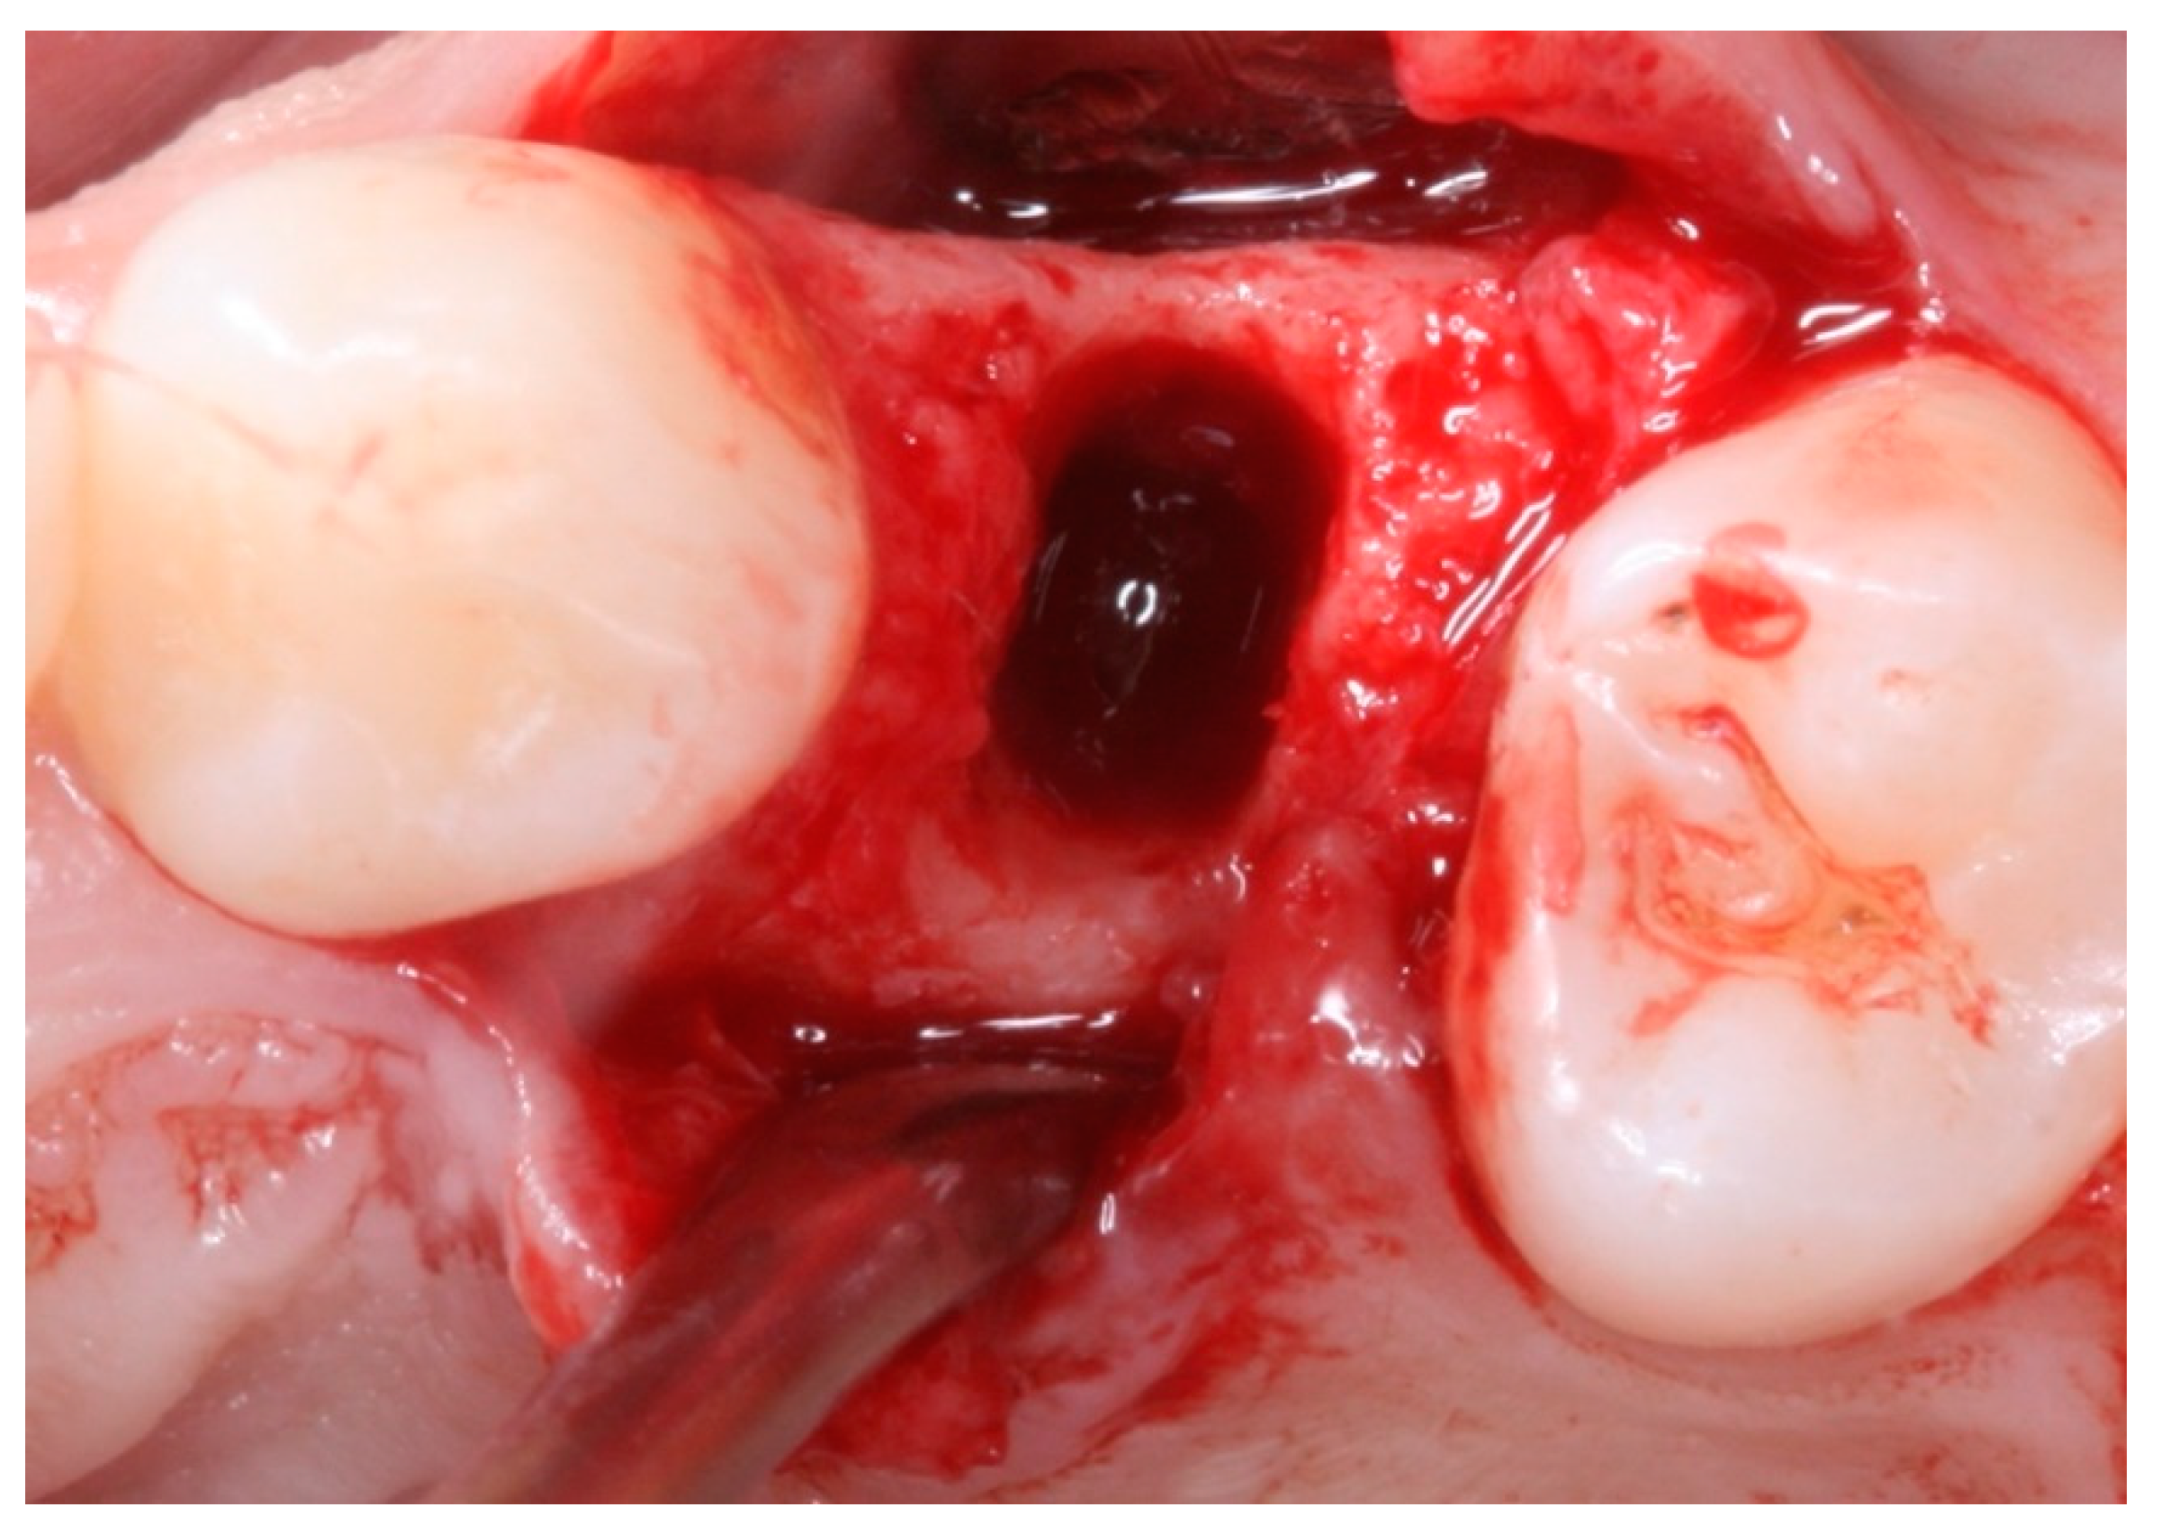

Socket Preservation Using a (Dense) PTFE Barrier with or without Xenograft Material: A Randomized Clinical Trial

2. Materials and Methods

2.4. Groups